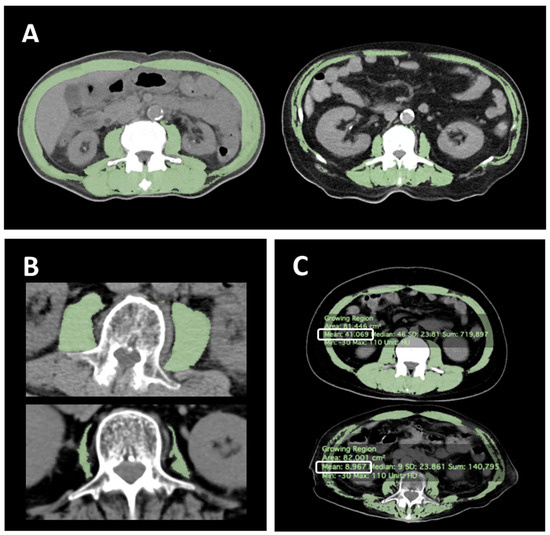

2.2. Diagnosis of Sarcopenia